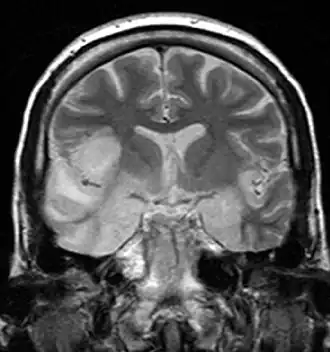

Uma ligeira pleocitose é normalmente detetável no líquido cefalorraquidiano; podem ocorrer bandas oligoclonais durante o curso da doença.[24] Os achados de RM são geralmente inespecíficos, não se correlacionam com os sintomas clínicos (pequenas lesões inespecíficas da substância branca nas áreas frontal, parietal e mesiotemporal; ocasionalmente tálamo, cerebelo e tronco cerebral, raramente gânglios basais) e são detectáveis na fase aguda em apenas cerca de 25-50% dos doentes. No entanto, os métodos de análise quantitativa podem detetar uma redução do volume do hipocampo[25] e alterações na substância branca utilizando imagens de difusão a longo prazo.[26] A maioria das crianças com encefalite NMDAR apresenta uma redução relevante do volume cerebral e um comprometimento do crescimento cerebral adequado à idade.[27] Através da ressonância magnética funcional (a chamada "ressonância magnética do estado de repouso"), foi recentemente demonstrado que, mesmo com imagens clínicas praticamente imperceptíveis, a organização intrínseca da rede pode ainda estar afetada anos após a encefalite NMDAR. [25][28][29]

A RM cerebral é um exame padrão essencial em doentes com suspeita de encefalite autoimune, especialmente para excluir possíveis diagnósticos diferenciais. Os achados da RM na encefalite autoimune são diversos. Por exemplo, na maioria dos doentes com encefalite NMDAR (até 75%), a RM não apresenta alterações; na degenerescência cerebelar paraneoplásica, a atrofia do cerebelo também só é detetável no decurso da doença.[42] Em doentes com encefalite límbica, por outro lado, é frequente encontrar imagens hiperintensas em T2/FLAIR unilaterais ou bilaterais do lobo temporal medial (MTL) - o que permite então (no caso de afeção bilateral) o diagnóstico de "encefalite límbica definitiva" (Tab. 3).[3] No caso de afeção unilateral, no entanto, o glioma deve ser considerado como um dos diagnósticos diferenciais.[48] No entanto, as hiperintensidades T2/FLAIR do MTL não podem ser detectadas em todos os doentes com encefalite límbica associada ao LGI1-Ak, embora quase todos os doentes desenvolvam atrofia do hipocampo durante o curso.[40] A extensão desta lesão hipocampal está correlacionada com a gravidade dos défices de memória persistentes na encefalite LGI1. No caso das crianças com encefalite NMDAR, foi demonstrado que as alterações da RMN na linha de base estão associadas a um pior resultado a longo prazo.[27] Uma revisão exaustiva de outras alterações imagiológicas (RM, PET) na encefalite autoimune pode ser encontrada em Heine et al.[42]